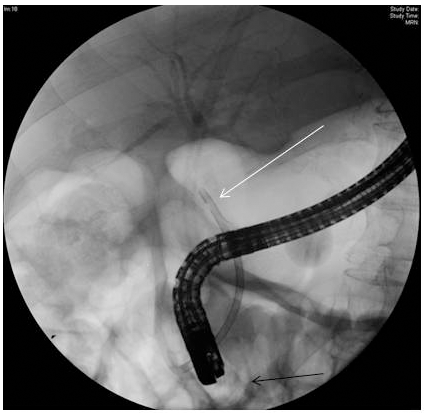

Figure 1: Endoscopic retrograde cholangiogram demonstrating impacted common bile duct stone.

Postpartum, the patient continued to have right upper quadrant abdominal pain and thus, an ERCP with a sphinterotomy was performed, which revealed impacted, large common bile duct stones that were not able to be removed. Although the patient delivered prior to biliary decompression via gallstone extraction and biliary stent placement, this intervention is often utilized as a temporizing maneuver until definite therapy can be instituted. Consequently, a biliary stent was placed for decompression to prevent cholangitis.